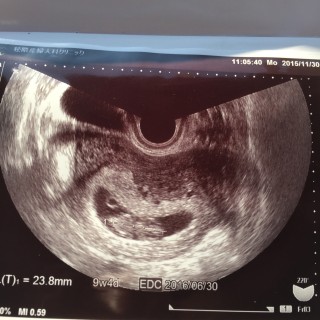

23,8mm。順調ですって言われました! 2頭身なのもはっきりわかって、ますます愛おしくなりました☆

前回7w4dのときは芋虫みたいな形で11mm。今回は9w4dで24mmに成長していました。2週間で本当に人の形になっていてびっくり!右手をぴょこぴょこ動かしてて心臓も脳もちゃんとできていて感動しました。次は1ヶ月後~元気に育ってね。